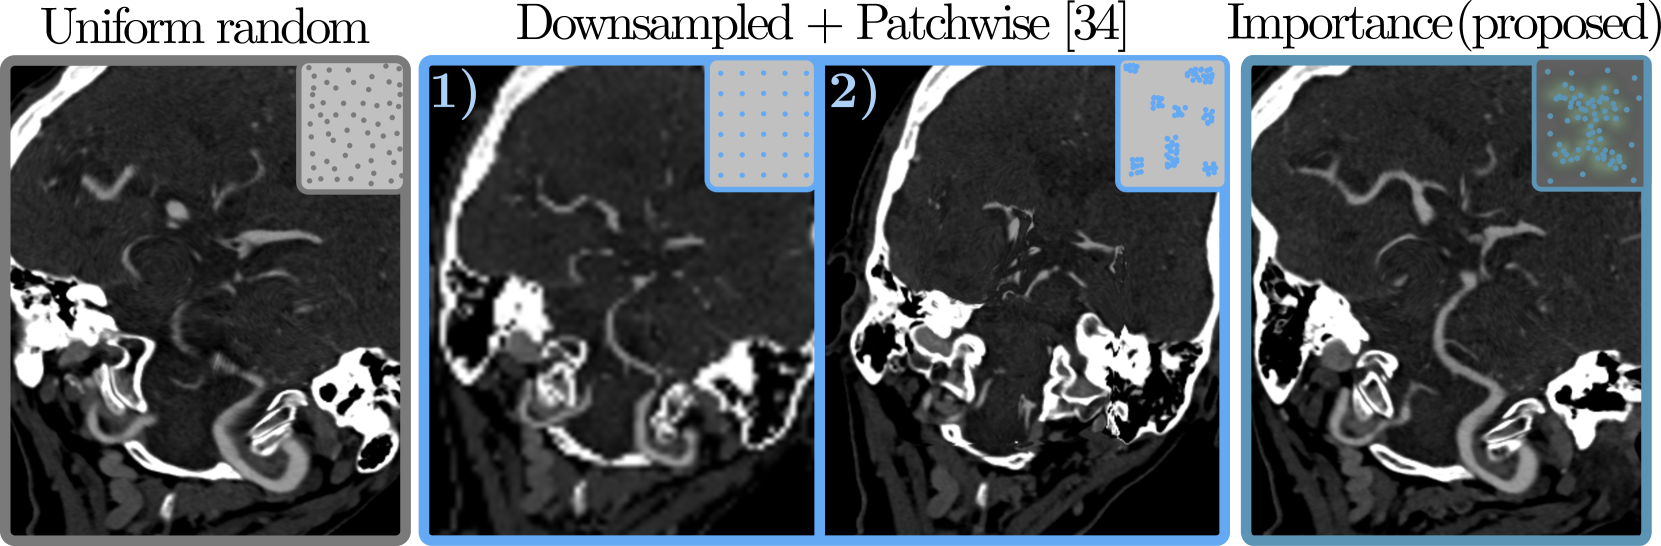

Refer to caption

Figure 3: Importance sampling (left) and map overlay (right) from an importance definition in volumetric space which is inversely proportional to the Euclidean distance to the target (green).

5.2 Importance Sampling & Map

Input sampling strategies for fitting neural fields in image registration include uniform [37] or downscaled (global) plus patchwise (local) schemes [34]. To accelerate fitting at relevant and more complex locations, we assign less importance to transformations distant to the targets. Proximity to target positions can be precalculated by applying the Euclidean Distance Transform e(I)𝑒𝐼e(I)italic_e ( italic_I ) to the volume grid. A volume of importance weights VE=|min(e(I)α,0)|+βα+βsubscript𝑉E𝑒𝐼𝛼0𝛽𝛼𝛽V_{\text{E}}=\frac{|\min(e(I)-\alpha,0)|+\beta}{\alpha+\beta}italic_V start_POSTSUBSCRIPT E end_POSTSUBSCRIPT = divide start_ARG | roman_min ( italic_e ( italic_I ) - italic_α , 0 ) | + italic_β end_ARG start_ARG italic_α + italic_β end_ARG inverts the distance map and clips values >>>α𝛼\alphaitalic_α, giving more weight to points close to the target while assigning a minimum value of β𝛽\betaitalic_β to the rest. Transforming a coarse input grid with the neural field and reading out VEsubscript𝑉EV_{\text{E}}italic_V start_POSTSUBSCRIPT E end_POSTSUBSCRIPT yields a 2D importance map E𝐸Eitalic_E, as shown in Fig. 3. We perform importance sampling by selecting points according to the distribution in E𝐸Eitalic_E, while ensuring coverage of all regions with β𝛽\betaitalic_β>>>00. Inspired by ADR [13], one can utilize the value of VE(𝐱^i)subscript𝑉Esubscript^𝐱𝑖V_{\text{E}}(\mathbf{\hat{x}}_{i})italic_V start_POSTSUBSCRIPT E end_POSTSUBSCRIPT ( over^ start_ARG bold_x end_ARG start_POSTSUBSCRIPT italic_i end_POSTSUBSCRIPT ) during model fitting as weighting factor wssubscript𝑤𝑠w_{s}italic_w start_POSTSUBSCRIPT italic_s end_POSTSUBSCRIPT in Eq. (4). This emphasizes small distortions close to the target and can help to move inevitable distortions to less important areas. We choose a fixed sampling size of 50k point pairs per epoch that are optimized in a single batch.

The influence on convergence of different sampling schemes (uniform-random, downsampled pretraining followed by patchwise fitting [34] and our importance sampling) is investigated using 500 samples for the first 500 epochs and is shown in Fig. 9 and Sup. Tab. 4. In early fitting stages, our oversampling of the target regions leads to more consistent centerline coverage (\approx 0.5 mm improvement on median target distance) with lower median distortion. In later stages, the effects become marginal compared to uniform-random. While downsampled pre-fitting results in a reasonable low-frequency approximation of the target vessels (e.g. 0.87 mm median distance in Fig. 9), the additional patch-wise sampling [34] does not converge to a meaningful solution for this task. We do not compare against sampling schemes that sample densely in regions with high error [10] as we intend to control the location of distortion.